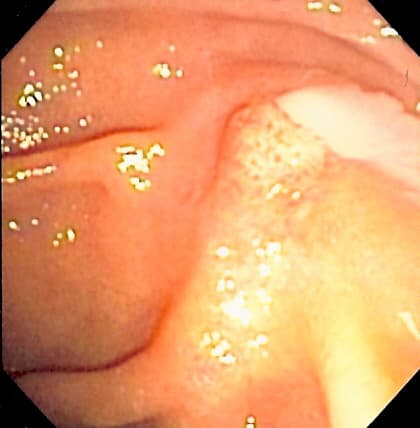

Langiocholite est une infection de la bile sur obstacle lithiasique obstruant la voie biliaire principale. Toute élévation de la pression au-delà de d'eau a pour conséquence une distension des voies biliaires qui se traduit sur le plan clinique par une douleur de type biliaire, la rétention de bile infectée des canalicules biliaires vers les sinusoïdes puis vers la circulation générale à travers le carrefour cavo-sus-hépatique : c'est le reflux cholangio-veineux, avec comme conséquence un ictère et une bactériémie (frissons). Dans les formes graves, la bile infectée se trouve sous une haute pression à l’intérieur des voies biliaires, la bactériémie est alors massive et répétée : c'est une véritable septicémie. La libération d'endotoxines bactériennes et des médiateurs leucocytaires de l'inflammation déclenche une cascade de réactions aboutissant à la défaillance uni- ou polyviscérale. Par ailleurs la rétention d'acides biliaires, néphrotoxiques, peuvent entrainer une insuffisance rénale aiguë (IRA) par nécrose tubulaire aiguë. Le reflux massif et répété de bile infectée à travers le foie fait que ses moyens d'épuration sont dépassés, il en résulte la formation d’abcès hépatiques abcès angiocholitiques). L'obstruction brutale de la voie biliaire principale (le plus souvent par un calcul biliaire issu de la vésicule, parfois par des parasites, ou par une tumeur type papillomatose) va entraîner la stase biliaire, avec la douleur de distension hépatique. Ce liquide de stase va se surinfecter, avec des risques de passages bactériémiques (proximité des pédicules portaux et des canalicules biliaires dans l'ensemble du foie ; importance du débit sanguin intra-hépatique). L'ictère va ensuite s'installer, progressivement, avec selles décolorées et urines foncées. Le risque principal est lié à la gravité et à la brutalité de l'infection, avec septicémie, choc septique, anurie et coma. C'est la classique triade de Charcot : douleur de type biliaire, fièvre à , et ictère progressant rapidement, ces signes s'installant l'un après l'autre en 48 heures.